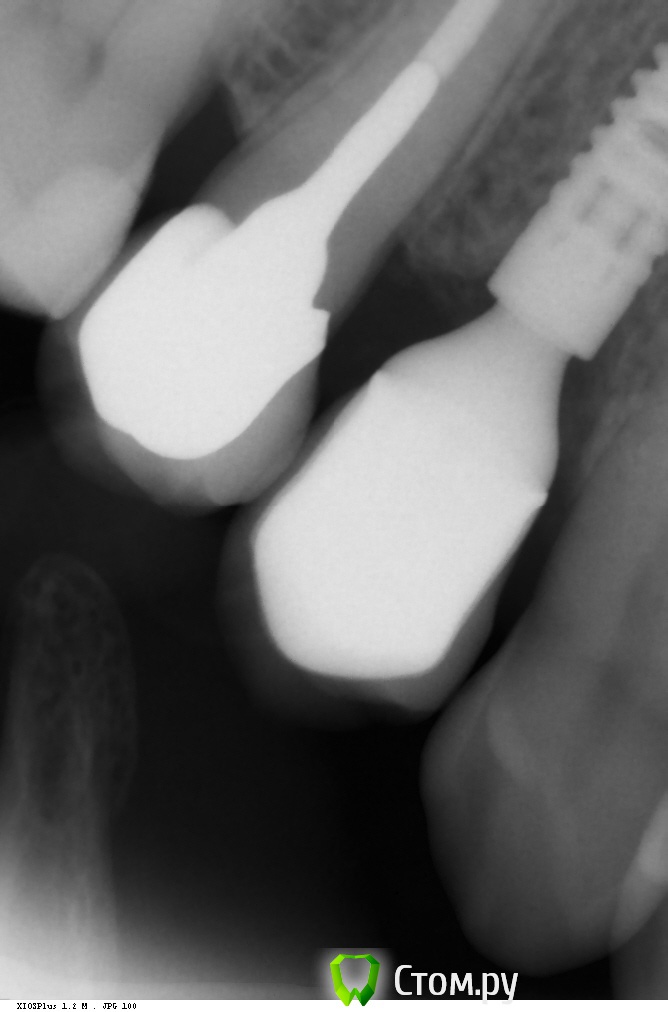

Фит на 15.

14 - одномоментно с удалением. медиально кость ушла? будут проблемы или нет? Дмитрий запугал вконец )